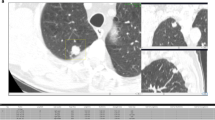

To compare unassisted and CAD-assisted detection and time efficiency of radiologists in reporting lung nodules on CT scans taken from patients with extra-thoracic malignancies using a Cloud-based system.

Three radiologists searched for pulmonary nodules in patients with extra-thoracic malignancy who underwent CT (slice thickness/spacing 2 mm/1.7 mm) between September 2015 and March 2016. All nodules detected by unassisted reading were measured and coordinates were uploaded on a cloud-based system. CAD marks were then reviewed by the same readers using the cloud-based interface. To establish the reference standard all nodules ≥ 3 mm detected by at least one radiologist were validated by two additional experienced radiologists in consensus. Reader detection rate and reporting time with and without CAD were compared. The study was approved by the local ethics committee. All patients signed written informed consent.

The series included 225 patients (age range 21–90 years, mean 62 years), including 75 patients having at least one nodule, for a total of 215 nodules. Stand-alone CAD sensitivity for lesions ≥ 3 mm was 85% (183/215, 95% CI: 82–91); mean false-positive rate per scan was 3.8. Sensitivity across readers in detecting lesions ≥ 3 mm was statistically higher using CAD: 65% (95% CI: 61–69) versus 88% (95% CI: 86–91, p<0.01). Reading time increased by 11% using CAD (296 s vs. 329 s; p<0.05).

In patients with extra-thoracic malignancies, CAD-assisted reading improves detection of ≥ 3-mm lung nodules on CT, slightly increasing reading time.